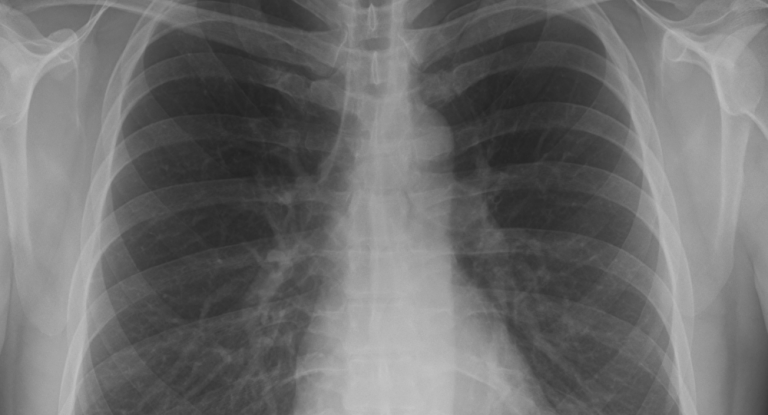

¿Qué ocurre en el cuerpo una vez que nos contagiamos de coronavirus? Artículos-Reportajes ¿Qué ocurre en el cuerpo una vez que nos contagiamos de coronavirus? martin 15 marzo, 2020 0 Sabemos que el SARS-CoV-2 está cada vez más extendido y conocemos las medidas que hay que tomar... Leer Más Leer más acerca de ¿Qué ocurre en el cuerpo una vez que nos contagiamos de coronavirus?